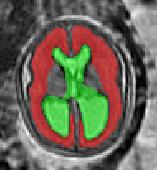

Limiting failures of machine learning systems is of paramount importance for safety-critical applications. In order to improve the robustness of machine learning systems, Distributionally Robust Optimization (DRO) has been proposed as a generalization of Empirical Risk Minimization (ERM). However, its use in deep learning has been severely restricted due to the relative inefficiency of the optimizers available for DRO in comparison to the wide-spread variants of Stochastic Gradient Descent (SGD) optimizers for ERM. We propose SGD with hardness weighted sampling, a principled and efficient optimization method for DRO in machine learning that is particularly suited in the context of deep learning. Similar to a hard example mining strategy in practice, the proposed algorithm is straightforward to implement and computationally as efficient as SGD-based optimizers used for deep learning, requiring minimal overhead computation. In contrast to typical ad hoc hard mining approaches, we prove the convergence of our DRO algorithm for over-parameterized deep learning networks with ReLU activation and a finite number of layers and parameters. Our experiments on fetal brain 3D MRI segmentation and brain tumor segmentation in MRI demonstrate the feasibility and the usefulness of our approach. Using our hardness weighted sampling for training a state-of-the-art deep learning pipeline leads to improved robustness to anatomical variabilities in automatic fetal brain 3D MRI segmentation using deep learning and to improved robustness to the image protocol variations in brain tumor segmentation. Our code is available at https://github.com/LucasFidon/HardnessWeightedSampler.